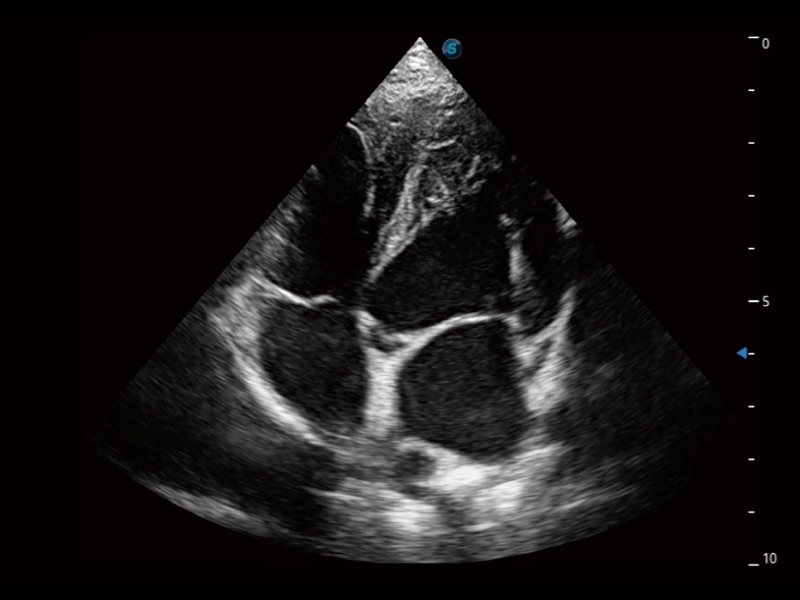

ProPet 70 進(jìn)一步提升了微米成像算法,更加注重對(duì)基礎(chǔ)原始圖像的還原和保留,在有效減少斑點(diǎn)噪聲、增強(qiáng)組織邊界顯示的同時(shí),避免過(guò)度優(yōu)化丟失真實(shí)的解剖信息。

ProPet 70專(zhuān)為動(dòng)物醫(yī)生設(shè)計(jì),對(duì)不同的動(dòng)物體型和生理結(jié)構(gòu)作出了針對(duì)性的優(yōu)化。通過(guò)動(dòng)物影像專(zhuān)用軟件,可滿足個(gè)性化的應(yīng)用需求,幫助動(dòng)物醫(yī)生獲得更精確的診斷數(shù)據(jù)。

為精細(xì)結(jié)構(gòu)及組織邊緣提供高清晰度的圖像和更大的成像視野。幫助減輕醫(yī)生的用眼疲勞,快速精準(zhǔn)獲得測(cè)量的數(shù)據(jù)。